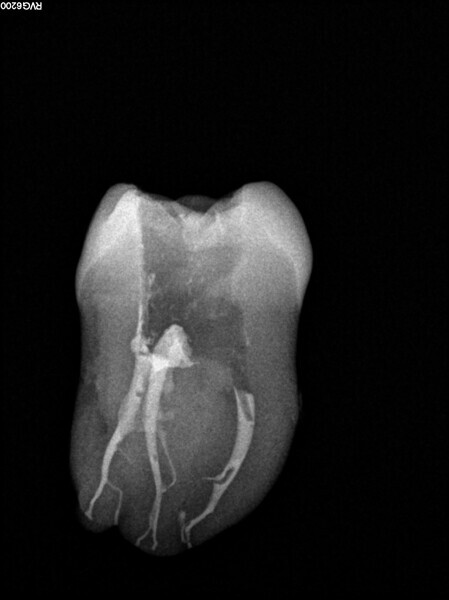

Post-op radiograph of a mandibular molar. (All Images: Bartłomiej Karaś)

A 25-year-old female patient presented to the office owing to constant pain related to the mandibular left first molar. Pulp necrosis was diagnosed. After the emergency appointment, the patient was referred for complete treatment. The tooth was treated in the same manner as described in the previous paragraphs. After creation of the access cavity, the orifices were located. In the root chamber, the orifices of the MB, mesiolingual, DB, distomesial and distolingual canals were present. After pre-flaring and preparation of the middle third, the LPE enhanced irrigation protocol with the SkyPulse laser was performed. After the irrigation protocol in the mesial root, the irrigants started to flow between lingual and buccal canals. Such an observation suggested to the operator that some space in the isthmus had been created. It is worth mentioning that at this stage apical enlargement was not performed. Final preparation of all five canals was performed with the reciprocating file, and the final irrigation protocol was performed as in the previous case. The radiograph clearly revealed that the isthmus space was filled with the sealer. The radiograph and CBCT image revealed that there were four portals of exit in the mesial root.